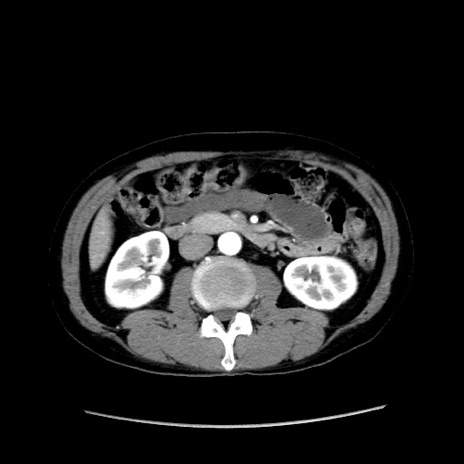

症例37(横断像)

【症例】40歳代 男性

【主訴】腹痛

【現病歴】4時間ほど前に電車に乗車中に臍部上より腹痛出現。徐々に増悪し起立困難となり、救急外来受診。生ものは数日食べていない。今朝お雑煮を食べた。

【身体所見】BT 36.8℃、BP 117/84mmHg、HR 91/min、SpO2 97%、苦悶様、腹部:臍上部広範囲圧痛あり、反跳痛±

【データ】WBC 8100、CRP 0.03